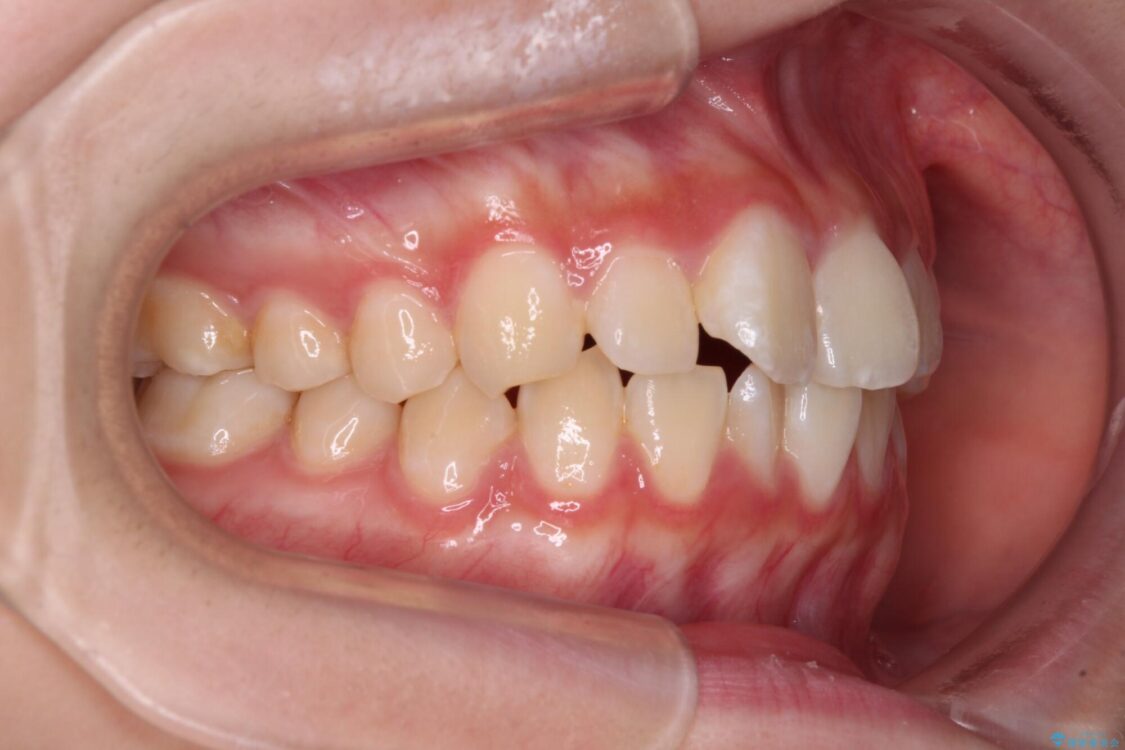

上下前歯のねじれを気にして来院された患者様です。

ワイヤー矯正でもマウスピース矯正でも対応可能でしたが、マウスピース矯正の自己管理が面倒であること、上顎前歯の捻転が著しいことから、ワイヤー矯正での治療を希望されました。

インビザライン治療が継続できない性別と年齢が世界的に調査されているそうですが、ほとんどの国で女子高生が最も多いとのことです。

治療前

• インビザラインは使える自信がない ワイヤー装置にて矯正治療 治療前画像